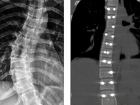

Ставропольские нейрохирурги провели сложную операцию по коррекции сколиоза 25.11.2025 Здоровье -